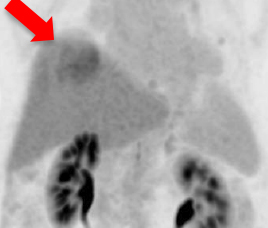

氟18 PSMA正电子/电脑双融扫描显示大部分病灶於鑥177 PSMA放射核素治疗後可见改善(红色箭头所示)。

治疗後扫描显示病灶活跃度大大降低。